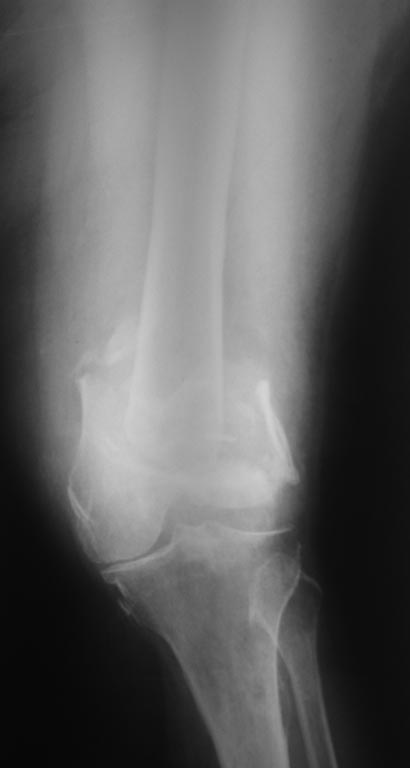

Перелом бедра у женщины 65 лет, случился 7 мес. назад( падение с высоты роста на колено) . Живет в деревне, лечил хирург, снимки ни разу не делали. Со слов больной после травмы в области коленного сустава была рана, долго заживала. Пациентка весит 120кг. В настоящее время передвигается в кресле коляске, правая нога не опорная.Снимки и внешний вид конечности прилагаются (свежие и единственные). Из сопутствующей патологии :ожирение 3ст, артериальная гипертензия и сахарный диабет 2тип, компенсация. Пациентка очень хочет самостоятельно передвигаться. Планируем выполнить артродез коленного сустава длинным штифтом( бедро-голень). Хотелось услышать ваше предложения и мнения по тактике, возможные варианты оперативного лечения.

План выглядит подходящим. Хотя, может статься, что после наложения дистрактора и восстановления длины появится возможность сделать антеградный интрамедуллярный остеосинтез. Может быть, и нет. Длинные стержни мы заказывали на предприятии ЦИТО.

Эндопротезирование ревизионным имплантатом тут тоже вполне можно рассматривать.

Здравствуйте коллеги! Идея с артродезированием длинным стержнем мне видится достаточно перспективной, при отсутствии проблем с его изготовлением и инструментом для имплантации. Чрескостный остеосинтез аппаратом Илизарова принципиально возможен, но учитывая массу тела больной и перспективу гофрировки мягких тканей при артродезе весьма рискован (ИМХО).